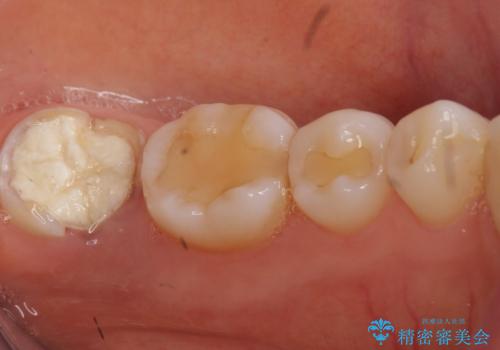

- 昔何回か根管治療した奥歯が膿んでいていて痛みがあることを主訴に来院された患者様です。

精査したところ、左下の奥歯にはひびが入っていて、保存不可能な状態でした。

割れている奥歯を抜去後左上の機能していない親知らずを移植し、生着したのち根管治療・補綴を行いました。